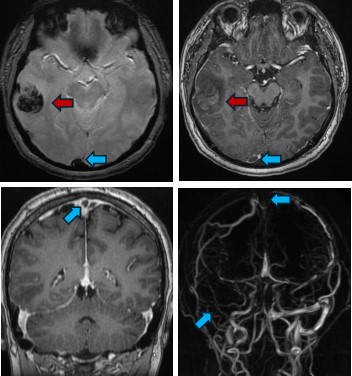

Hình ảnh MRI sọ não của bệnh nhân: Xuất huyết não vùng thái dương phải (nũi tên đỏ); Huyết khối xoang tĩnh mạch dọc trên, xoang ngang – xoang sigma, tĩnh mạch vỏ não đính 2 bên (mũi tên xanh)